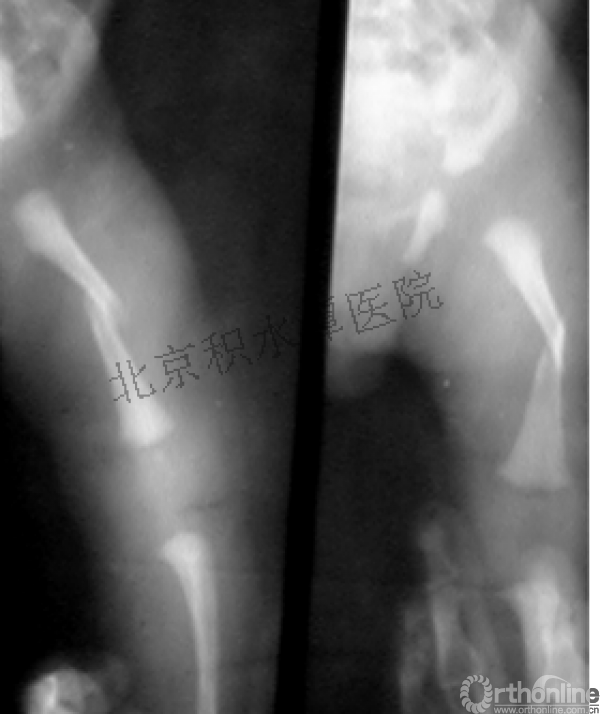

髁上骨折

跨骺板固定

伤后4年

病例分享三

男孩、9岁,滑雪受伤,胫腓骨螺旋形骨折(粉碎性)

这个病例郭教授在积水潭医院骨科高研班时多次讲到,也在互动交流中惊人地看到,了解到现实之令人难以想象!

手法整复,石膏制动!

整复后7天

儿童具备强大的愈合潜力,同样也有极强的塑形能力

某种情况下,The best treatment is no treatment! 最佳治疗反而是不治疗!因为很多骨折依靠儿童强大的塑形能力和特点完全可以得到满意的结果!